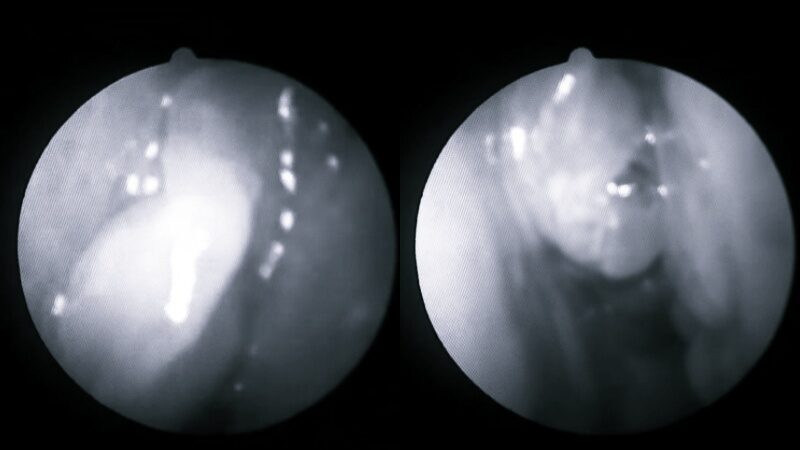

นพ.ติง เหมิงชาง กล่าวว่า เมื่อเขาใช้กล้องเอนโดสโคปเพื่อสำรวจโพรงจมูกด้านซ้ายของคนไข้ชายคนนั้นก็รู้สึกประหลาดใจที่เห็นก้อนเนื้อที่ชัดเจนมาก เมื่อดูจากสี จริง ๆ แล้วคาดว่าเป็นติ่งเนื้อจมูกธรรมดาในตอนแรก แต่เนื่องจากมีอาการเลือดออกอย่างเห็นได้ชัดจึงเป็นการยากที่จะเพิกเฉย

ดังนั้น แพทย์แนะนำให้ผู้ป่วยเข้ารับการตรวจชิ้นเนื้อเพื่อยืนยันว่าเป็นเนื้องอกเนื้อร้ายหรือไม่ จากนั้นผู้ป่วยได้รับการวินิจฉัยว่าเป็นเนื้องอก มะเร็งในโพรงจมูก และต่อมาผู้ป่วยก็ถูกส่งตัวไปที่ศูนย์การแพทย์เพื่อรับการรักษา